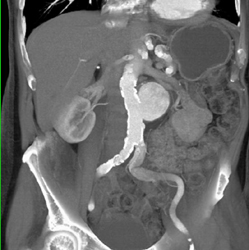

DIEP Protocol Study